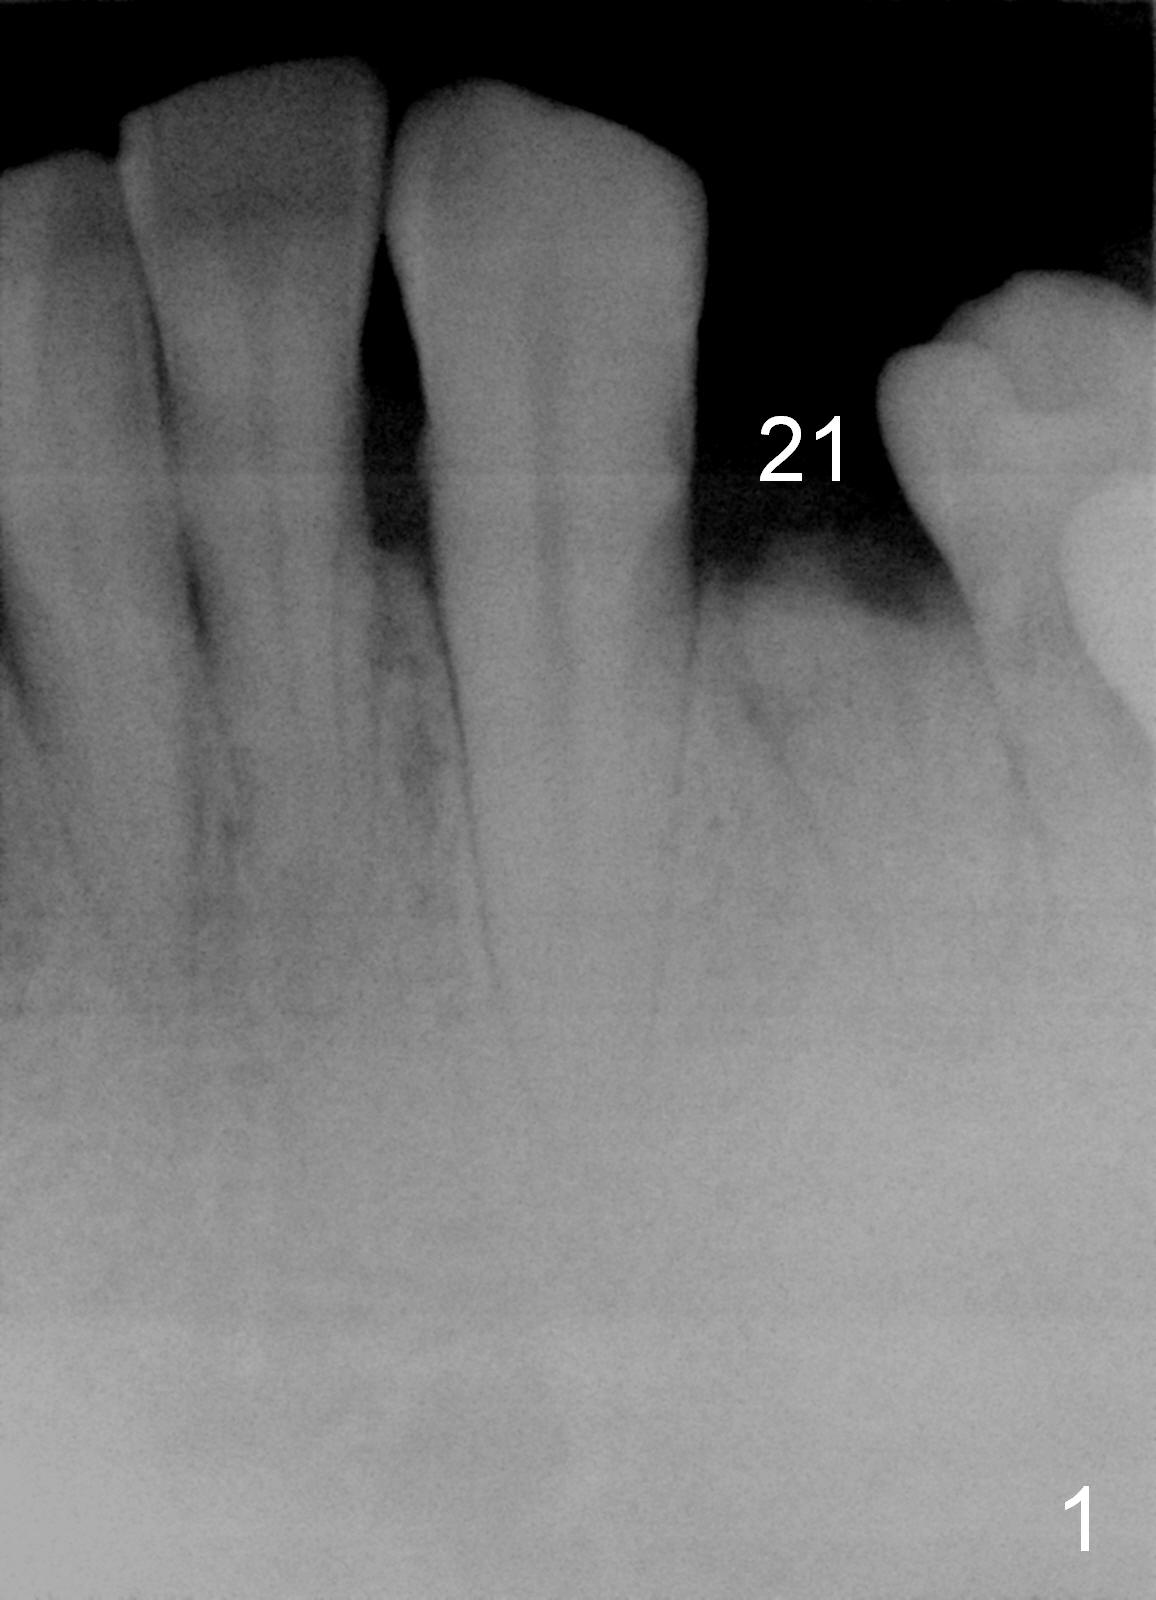

A 48-year-old man requests restoring the fractured tooth #21 (Fig.1). The socket seems to be oblique (Fig.2, no Antibiotic). Also considering the thin buccal plate, the initial osteotomy should be established in the mesiolingual slope (Fig.3). Change the trajectory once the entry is made (Fig.4) and take PA for confirmation. A 4x13 mm implant is to be placed (Fig.5). Why should the implant placed lingually? In fact the implant is placed too lingually. What is the reason?